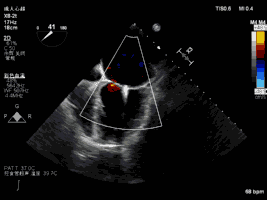

夾合術(shù)后:彩色多普勒示輕微二尖瓣反流

2019年3月5日中午,復(fù)旦大學(xué)附屬中山醫(yī)院葛均波院士團(tuán)隊(duì)的周達(dá)新教授、潘文志副主任醫(yī)師,心外科的魏來(lái)教授、楊曄主治醫(yī)師,心超室的潘翠珍教授、李偉主治醫(yī)師,麻醉科的郭克芳教授,使用最新一代心臟超聲機(jī)器Philips EPIQ 7C,完成一例經(jīng)心尖二尖瓣夾合術(shù)。新一代超聲機(jī)器分辨率高,圖像處理速度快,圖像界面舒適,使得手術(shù)非常順利。導(dǎo)管操作時(shí)間(從穿刺心尖到閉合心尖時(shí)間)僅10分鐘?;颊咝g(shù)后即刻效果滿意,反流從重度減少到輕微。本例是國(guó)內(nèi)首例使用最新一代心超機(jī)器Philips EPIQ 7C的X8-2t食道探頭進(jìn)行術(shù)中經(jīng)食道超聲,采用TrueVue心腔鏡成像技術(shù)指導(dǎo)心臟介入手術(shù),獲得滿意的結(jié)果。